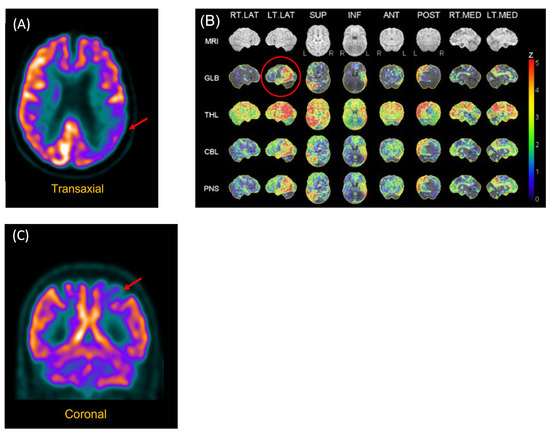

The following problems were noted by the geriatrician during an examination performed in 2017: empty speech with word-finding difficulties manifested by vague terms and hesitations, calculation and number processing (comprehension of magnitude) difficulties, ideomotor apraxia, and digital agnosia. MRI showed white-matter periventricular hyperintensities and volume loss in the bilateral temporal lobes, while an FDG-PET scan showed hypometabolism of the left polymodal associative areas, especially the parieto-occipital regions, as well as asymmetry (left > right) of the primary visual areas (see Figure 1).

Structural neuroimaging (CT brain) was normal. However, functional neuroimaging (FDG-PET scan) showed hypometabolism of the left posterior parietal region (see Figure 1).

Figure 1. FDG-PET Scan of P2 and P3. (A) P2. Reconstructed slices showing hypometabolism of the left polymodal associative areas, especially the parieto-occipital regions, as well as asymmetry (left > right) of the primary visual areas. (B) P2. Statistical analysis of metabolism distribution as compared to marched normal database showing areas of hypometabolism in the left hemisphere, including in the left posterior temporal region (image circled in red). (C) P3. Hypometabolism of the left posterior parietal region.